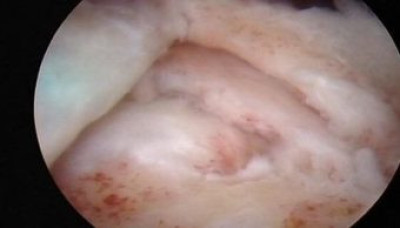

Se ha preparado el lecho óseo para iniciar la reinserción por medio de colocación de tornillos previamente cargados con hilos